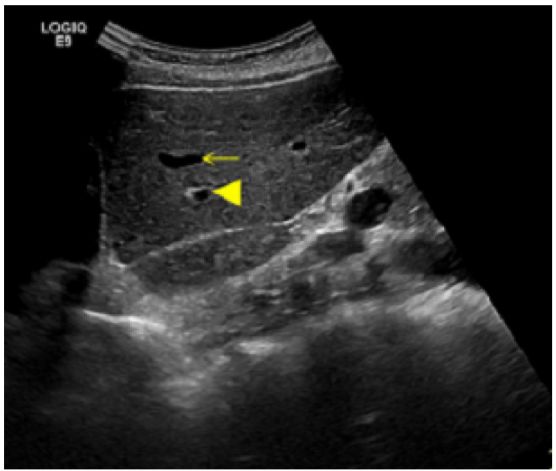

62.附圖為肝臟超音波影像,箭頭(◄)以及箭號(←)所指分別為何? (A)肝靜脈、門靜脈 (B)兩者皆為肝靜脈 (C)兩者皆為門靜脈 (D)門靜脈、肝靜脈